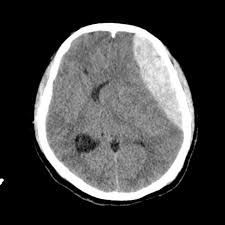

In most cases, your doctor will recommend surgery to remove an epidural hematoma. It usually involves a craniotomy. In this procedure, your surgeon will open up part of your skull so they can remove the hematoma and reduce the pressure on your brain. In other cases, your doctor may recommend aspiration.